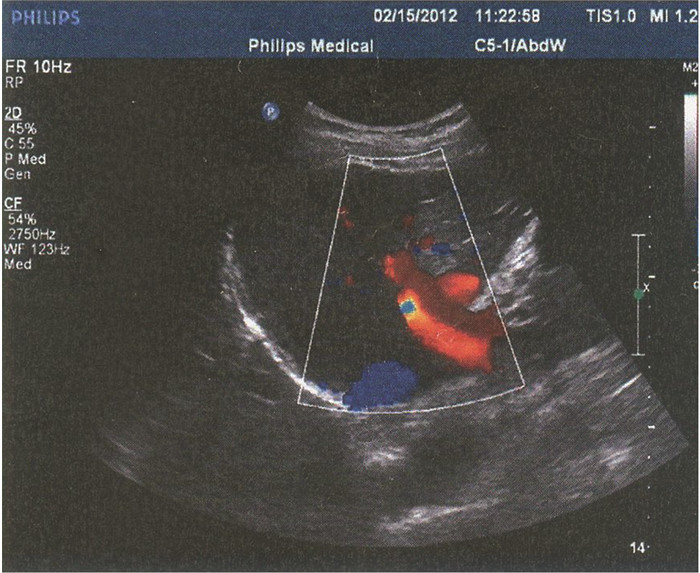

门静脉性胆道病1例报告

姜朋, 王树鹏, 刘亚辉

2022, 38(2): 430-432. DOI: 10.3969/j.issn.1001-5256.2022.02.034

摘要(724) HTML (240) PDF (2686KB)(54)

摘要: